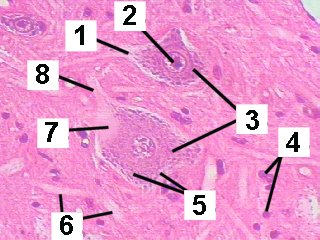

A higher magnification of the gray matter demonstrating anterior motor neurons.

Fig 026-004 |